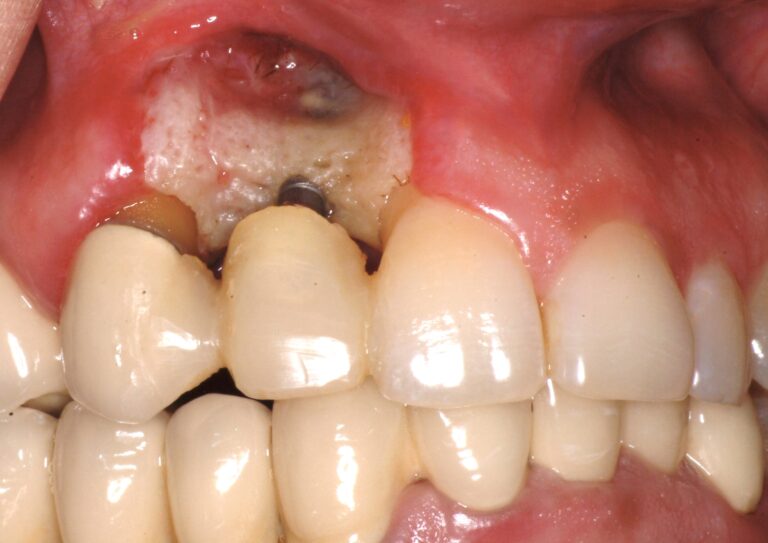

lecture 5: The Art of Anterior Implants

The Art of Anterior Implants

Course Outline

This anterior implant lecture is designed to provide practitioners with the knowledge and skills necessary to start planning and placing anterior implants in their offices. Understanding the complexity of anterior implants- including when to refer- is crucial for surgical and restorative outcomes. This lecture will focus on treatment planning and utilizing digital technologies such as CBCT imaging, intra-oral scanning, planning software, and surgical guides. Extraction, bone grafting, surgical technique, and suturing will be covered.